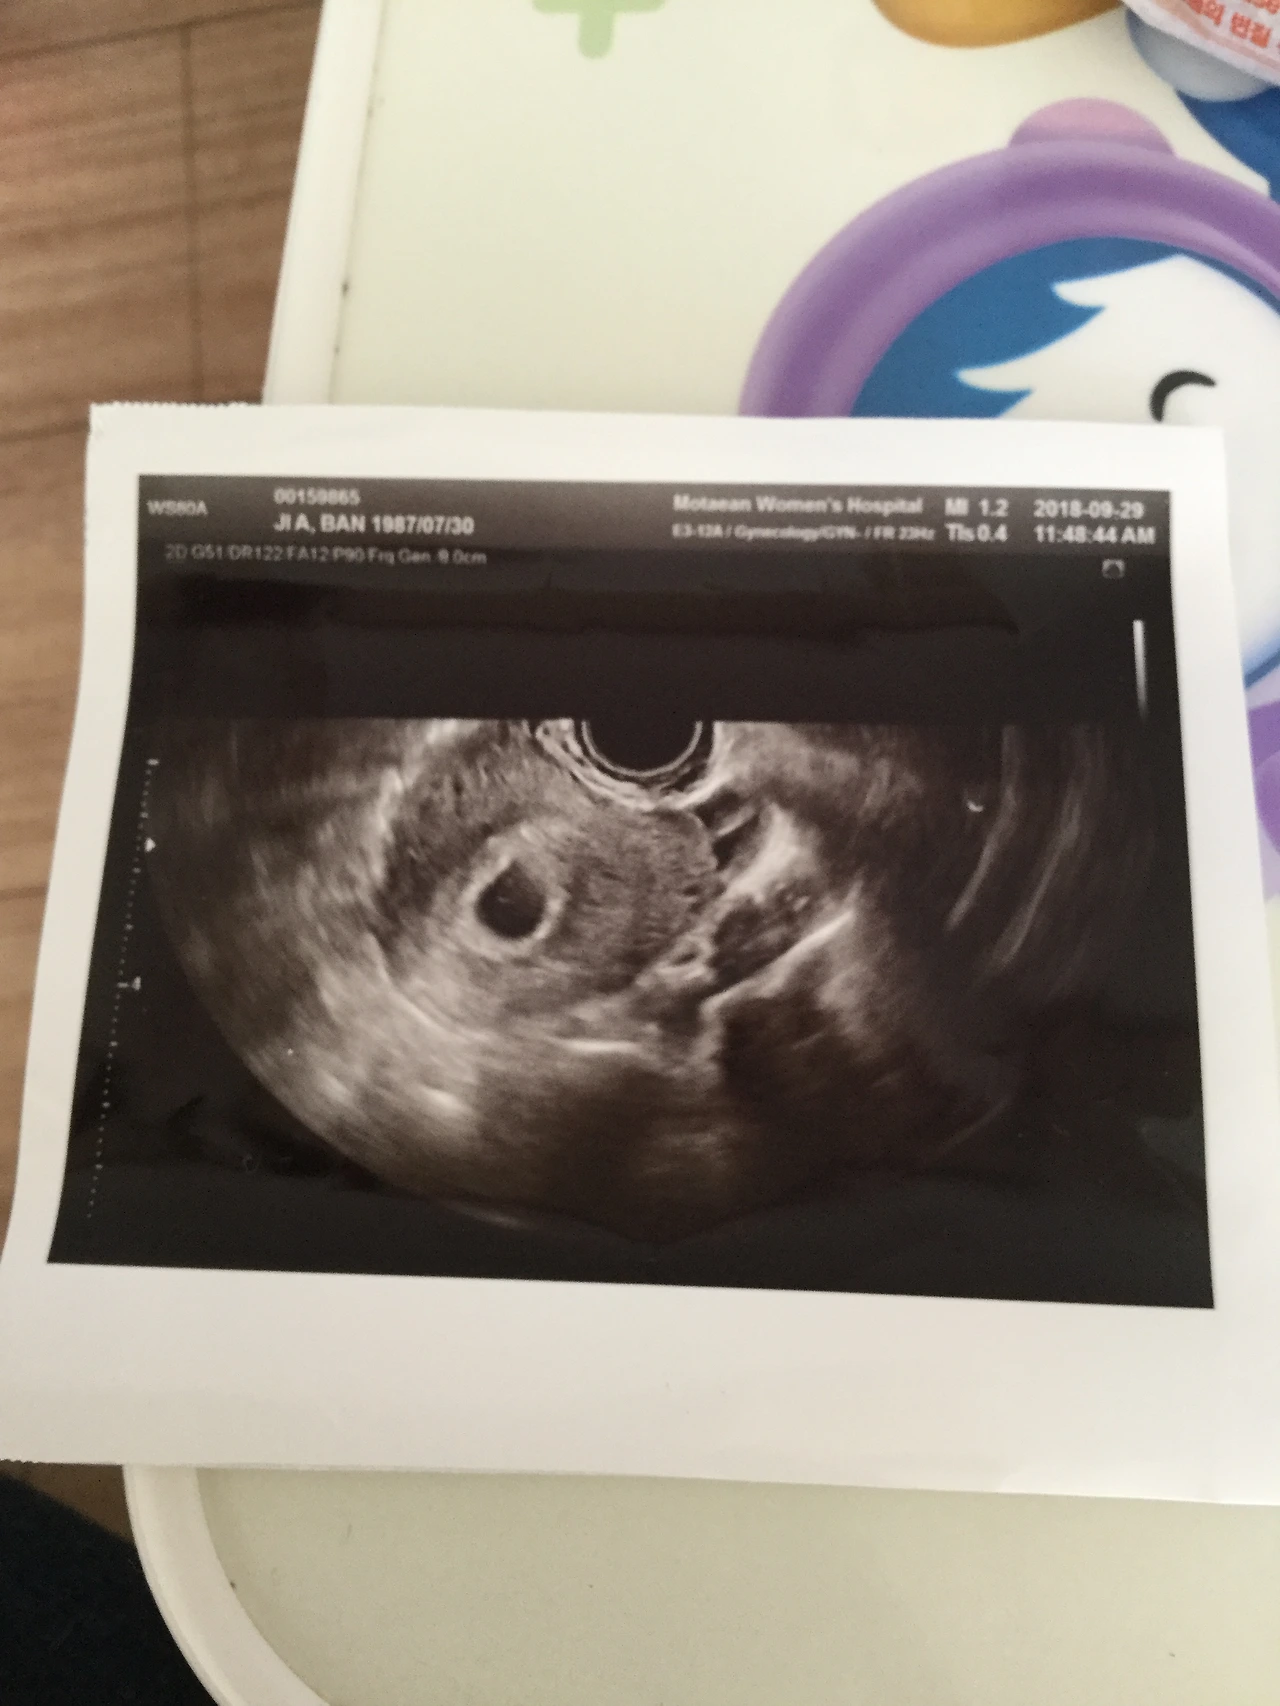

지금이야 다온이 한명이니까 남편이랑 둘이 번갈아가며 돌보지만 라온이가 태어났는데

그나저나 둘째는 첫째 책읽어주는게 태교고 첫째랑 하하호호하는게 태교라는데

진짜 그런가보다. 다온이가 있으니 내가 임신한걸 까먹을 정도는 아니지만 아직 제대로된

태담 한번을 안해줬다 ㅜㅜ

라온이 미안 ㅜㅜ